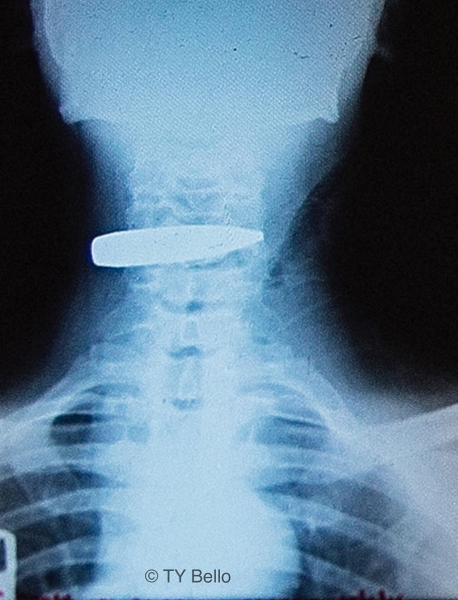

She also shared a photo of an xray showing an anti aircraft bullet lodged in a soldiers throat as she wrote the heart wrenching piece below…

I’ll share all their stories here and start by introducing Soldier X, who I never met, but made a photograph of his Xray .An anti aircraft bullet, big and strong enough to tear through the titanium body of an airplane, was lodged in his throat, and for some reason, it didn’t blow his head off, this soldier lived through his surgery and got to take the removed bullet home as a reminder. This is a wicked wicked war! Why would anyone chose weapons made to attack war planes and use it on a fellow human at close range, even in war there should be rules .